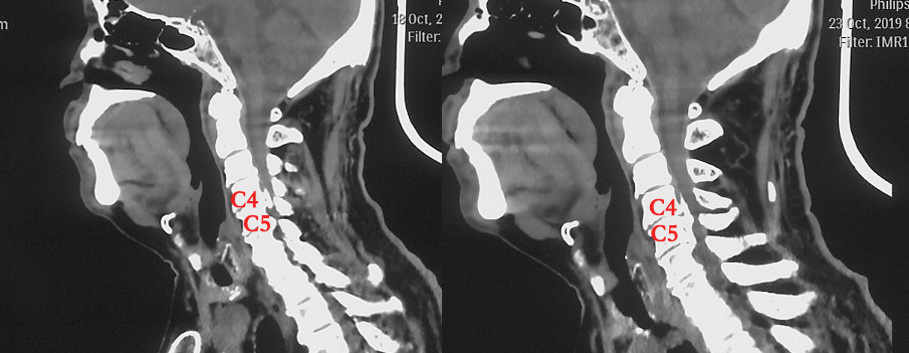

本期为大家分享荣获2019年度“精艺求菁-神经外科青年医师手术技能大赛”脊髓脊柱手术组季军的优秀病例,由解放军总医院第六医学中心张雷鸣医师带来的:脊柱内镜后路半椎板减压治疗颈椎后纵韧带骨化症,王贵怀教授、王振宇教授、车晓明教授及王劲教授点评。欢迎观看、分享。